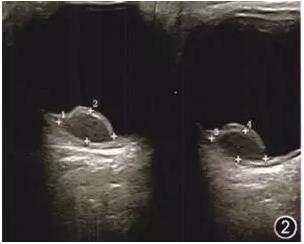

入院后行彩色多普勒超声检查示右眼视乳头鼻上方突向玻璃体实性半球形病变,基底直径8.4 mm,高度4.4 mm,边界清晰,内回声尚均匀,彩色多普勒血流成像可探及较丰富血流信号,玻璃体可探及弱点状回声及带状回声与其相连,彩色多普勒血流成像可见血流信号,考虑右眼球内实性占位病变;右眼玻璃体混浊;右眼继发性视网膜脱离(图2)。

图2 右眼视力下降患者右眼彩色多普勒超声图像,图中+示肿瘤边界,数字示肿瘤径线测量标识